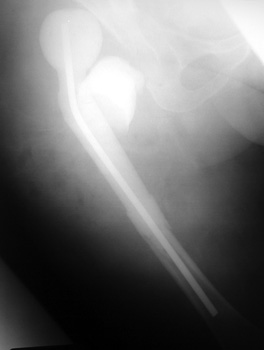

INFECTION

Resection of hardware, flail hip